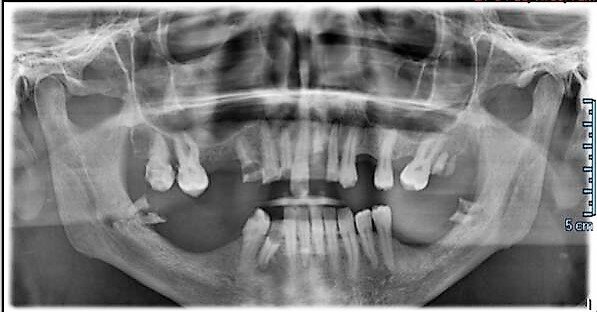

Descriviamo il caso di un paziente maschio di 56 anni con diagnosi di parodontite moderata generalizzata (Figg. 1-3), affetto da Diabete Mellito II in fase di scompenso (HbA1C 8,4%). Oltre alla malattia diabetica diagnosticata da 12 anni, il paziente presentava in anamnesi insufficienza renale, pregresso infarto miocardico acuto e storia di ipertensione arteriosa. I dati anamnestici hanno guidato la scelta dell’iter terapeutico da parte del team odontoiatrico.

Il paziente è stato sottoposto a rivalutazione 14 giorni successivi alla prima seduta (Fig. 4), durante la quale si rilevavano segni flogistici persistenti; è stata pertanto data indicazione al paziente di eseguire sciacqui con clorexidina 0,06% associata a cetilpiridinio cloruro 0,05% (GUM® Paroex® 0,06% CHX + 0,05% CPC), indicata per un uso quotidiano, sino al termine del trattamento parodontale non chirurgico e avulsione degli elementi dentali compromessi, eccetto che nel giorno dell’intervento per non interferire con la stabilizzazione del coagulo. Il paziente è stato quindi sottoposto a controllo delle condizioni di igiene orale settimanalmente per 4 settimane consecutive. La rivalutazione parodontale a distanza di tre mesi dal trattamento parodontale non chirurgico ha evidenziato un significativo miglioramento dell’aspetto delle mucose (Figg. 5, 6), quale segno tangibile della risoluzione della flogosi, e riduzione della profondità di tasca al sondaggio parodontale. Inoltre, si è potuto apprezzare una riduzione dei valori di emoglobina glicosilata (HbA1C) pari a 0,4%. Il paziente è sottoposto a controllo parodontale e debridement sopragengivale a intervalli trimestrali, seguito da sciacqui con clorexidina 0,12% associata a cetilpiridinio cloruro 0,05% (GUM® Paroex® 0,12% CHX + 0,05% CPC), per 30 secondi 2 volte/die per 7 giorni dopo la seduta di scaling.